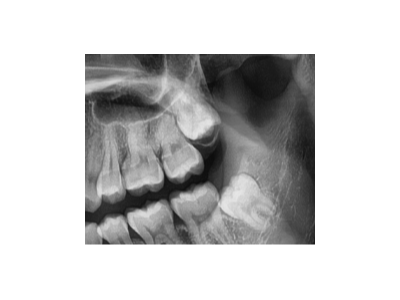

根管治療的全過程主要包括術(shù)前檢查和診斷、局部麻醉、開髓、根管預(yù)備、根管消毒,以及根管充填、術(shù)后修復(fù)。1、術(shù)前檢查與診斷:患者先到口腔科進(jìn)行全面檢查,包括患牙的齲壞程度、牙髓活力測(cè)試、叩診等,以確定患牙…

種植牙是一種常見的牙齒修復(fù)方式,術(shù)前準(zhǔn)備對(duì)于手術(shù)的成功和術(shù)后恢復(fù)至關(guān)重要。以下是種植牙術(shù)前的主要準(zhǔn)備工作:一、全面口腔檢查與評(píng)估口腔檢查:包括牙齒、牙齦、咬合關(guān)系、頜骨狀況等。影像學(xué)檢查:全景片(曲面…